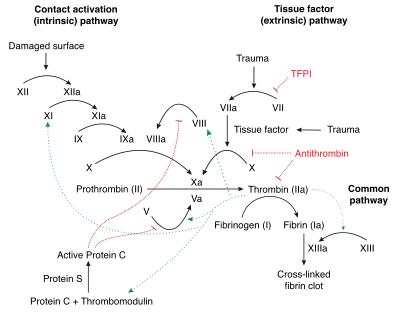

Normal coagulation is initiated by the release of tissue factor from damaged tissue. Tissue factor binds to circulating factor VIIa. The combination activates factor X to factor Xa and factor IX to factor IXa. Factor Xa (in the presence of factor V) activates prothrombin into thrombin. Thrombin is a central enzyme in the coagulation process: it generates fibrin from fibrinogen, and activates a number of other enzymes and cofactors (factor XIII, factor XI, factor V and factor VIII, TAFI) that enhance the fibrin clot.[13] The process is inhibited by TFPI (which inactivates the first step catalyzed by factor VIIa/tissue factor), antithrombin (which inactivates thrombin, factor IXa, Xa and XIa), protein C (which inhibits factors Va and VIIIa in the presence of protein S), and protein Z (which inhibits factor Xa).[13]

In thrombophilia, the balance between "procoagulant" and "anticoagulant" activity is disturbed. The severity of the imbalance determines the likelihood that someone develops thrombosis. Even small perturbances of proteins, such as the reduction of antithrombin to only 70–80% of the normal level, can increase the thrombosis risk; this is in contrast with hemophilia, which only arises if levels of coagulation factors are markedly decreased.[13]